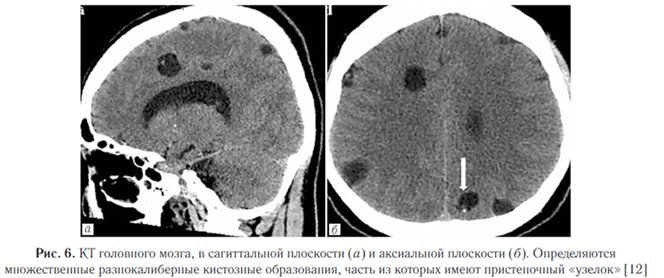

2. Везикулярная стадия (активная). Визуализи - руется полностью выросшая киста или скопление кист (по типу «грозди винограда») в базальных ганглиях, мозжечке, стволе мозга, цистернах или желудочковой системе, в паренхиме полушарий и в субарахноидальных пространствах. Сколекс встречается почти в 50% случаев. НЦЦ по типу «грозди винограда» наблюдается обычно вокруг рострального ствола мозга или сильвиевой щели, обычно лишен сколекса. Отек практически отсутствует (рис. 1).

Является второй по распространенности формой НЦЦ. Ряд авторов ставят его на первое место [10]. Наиболее частая локализация — на границе серого и белого вещества, что обусловлено накоплением паразита в мелких кровеносных сосудах, которые здесь локализуются. Однако на основании гистопатологического анализа некоторые авторы предполагают, что данный тип ЦЦС соответствует субарахноидальной форме заболевания, при этом паразиты локализуются в глубоких бороздах или в области периваскулярных пространств (рис. 6). Паренхиматозное поражение чаще имеет благоприятный прогноз, преимущественно проявляется судорогами и головной болью, которые со временем могут проходить самостоятельно [13]. В литературе указываются также психиатрические симптомы, но данное проявление является достаточно редким и встречается не более чем в 5% случаев НЦЦ [14]. Васкулит и арахноидит.